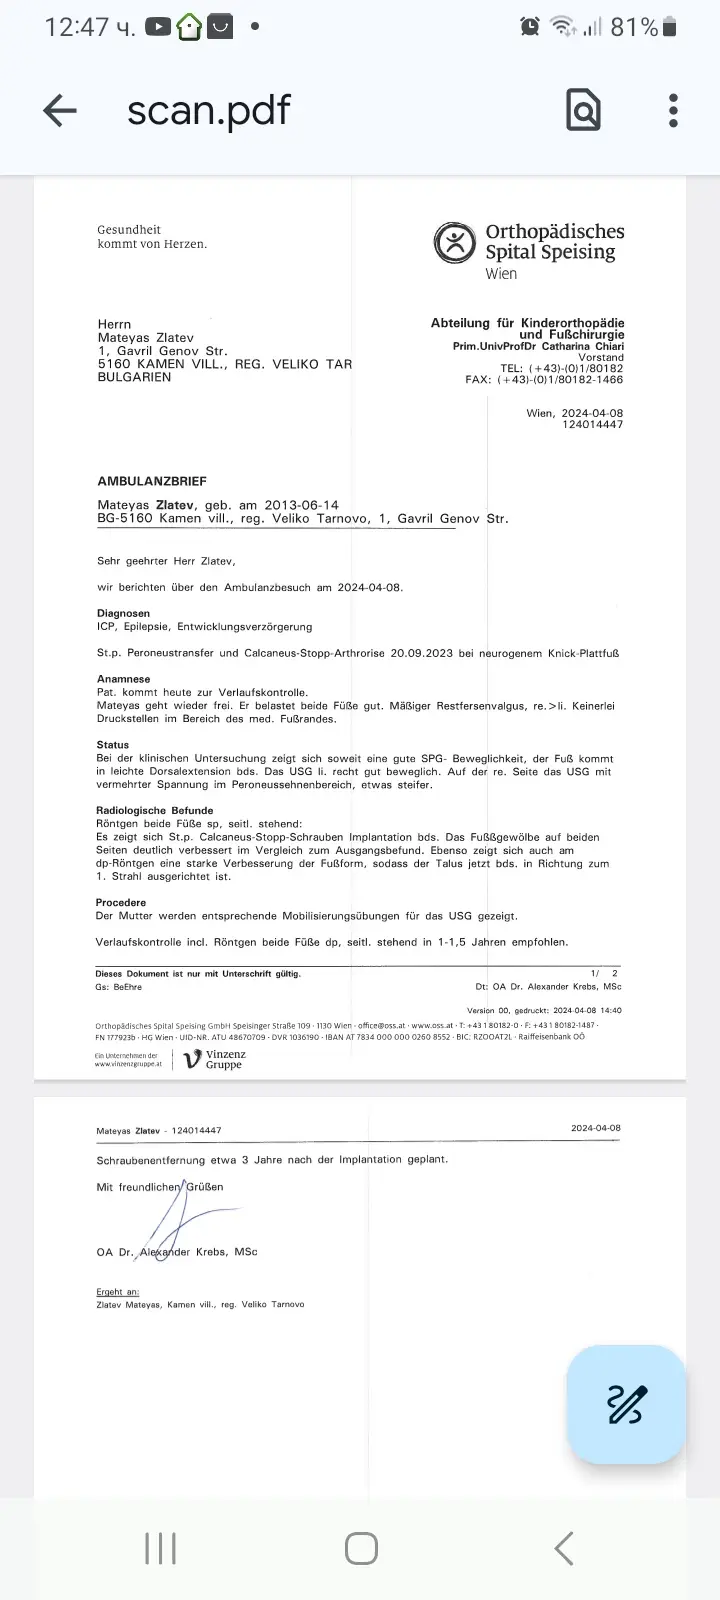

На 08.04.2024 бяхме на контролен преглед в Виена болница Шпайзинг при д-р Кребс. Минаха 6 месеца от операциите който Матеяс претърпя на свойте крачета веднъж 10 операции. Матеяс се възстановява по добре от очакваното. Лекаря му направи 4 бр рентгенови снимки и ни каза че към момента лечението върви по добре от очакваното и че не е очаквал такива добри и бързи резултати.

Препоръча ни да продължаваме с рехабилитацията и нощните шини Матеяс трябва да ги носи поне 4 години. Което ще рече че след няколко месеца ще трябва да поръчаме нови шини. Лекаря ни очаква догодина през пролетта или най късно през есента за преглед и изледвания и тогава ще се насрочи и операцията по свалянето на винтовете и имплантите. Има голяма вероятност тази операция да се направи по рано от предвиденото но всичко зависи от заздравяването на костта.

On 08.04.2024 we had a check-up in Vienna Hospital Speising with Dr. Krebs. It's been 6 months since Mateias had 10 operations on his legs. Mateias is recovering better than expected. The doctor took 4 x-rays and told us that the treatment is going better than expected and that he did not expect such good and fast results.

He advised us to continue with the rehabilitation and the night splints Mateyas should wear for at least 4 years. Which will mean that in a few months we will have to order new splints. The doctor is expecting us next spring or fall at the latest for a checkup and tests and then we will schedule the surgery to remove the screws and implants. There is a good chance that this surgery will be done sooner than scheduled but it all depends on the healing of the bone.